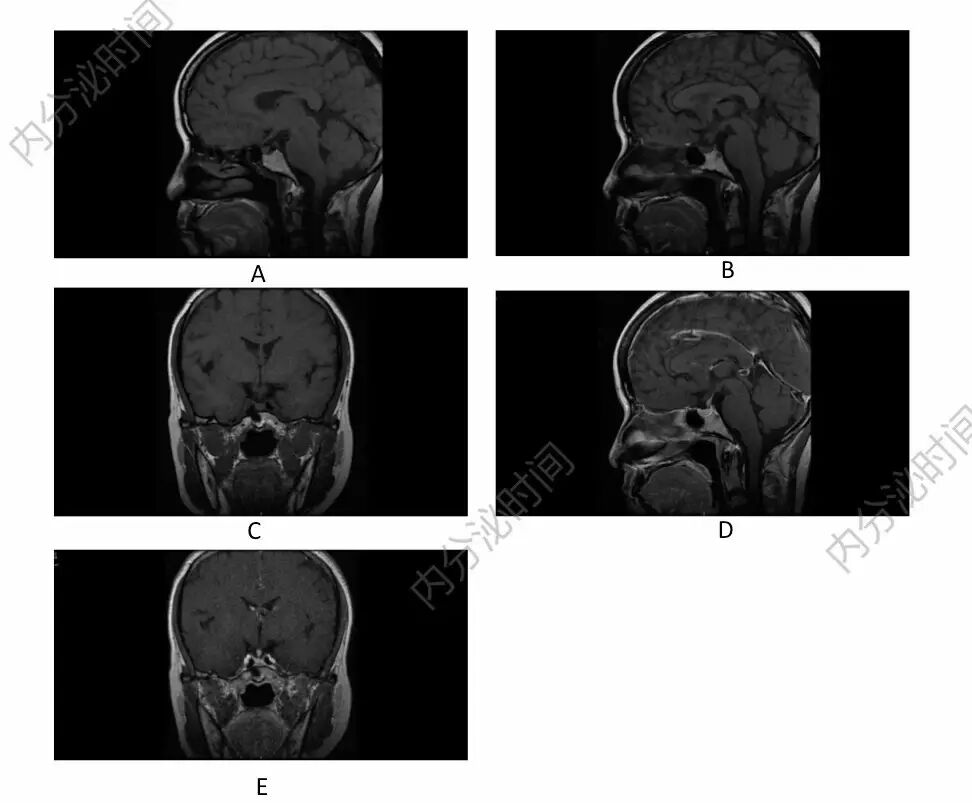

患者为什么发生中枢性尿崩症?只有请垂体 MRI 帮忙。MRI 平扫(见图 A,B,C)示垂体后叶形态及高亮信号未见显示,垂体前叶无异常,垂体柄居中,垂体柄中部可见局限性增粗,静脉注射 Gd-DTPA 后(见图 D、E),可见垂体均匀强化,无异常强化灶,垂体柄中部结节状增粗。

图 A 示 T1Wl 平扫矢状位:垂体后叶形态及高亮信号未见显示;图 B 示 T1Wl 平扫矢状位:垂体前叶未见异常;图 C 示 T1Wl 平扫冠状位:垂体柄居中,垂体柄中部可见局限性增粗;图 D、E 示静脉注射 Gd-DTPA 后,可见垂体均匀强化,无异常强化灶,垂体柄中部结节状增粗